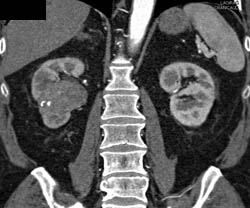

Transitional Cell Carcinoma